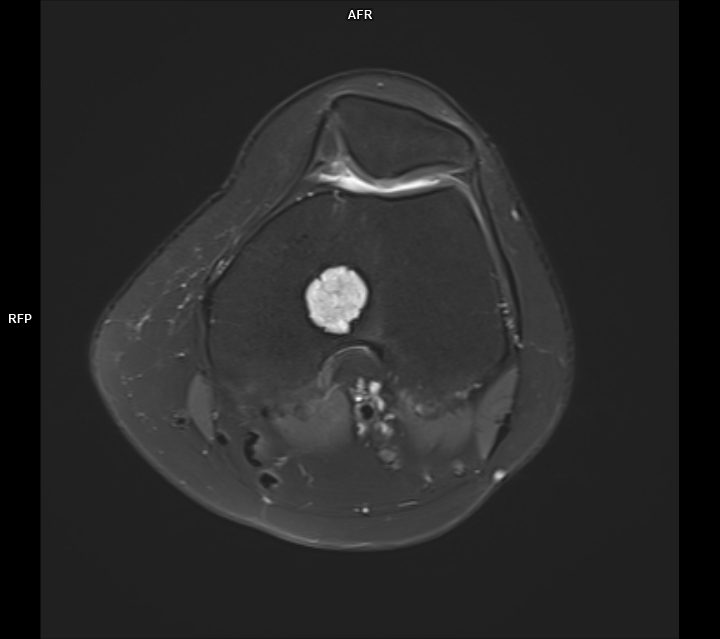

CAZ nr 44 Encondrom femural distal

Figura 3: achiziție în plan axial în ponderație PD cu saturația grăsimii

Discuție caz nr 44: Encondromul este o tumora benignă cu origine cartilaginoasă; cazul prezentat evidențiază o leziune net delimitată în hipersemnal PD, hiposemnal T1, fără restricție de difuzie, ce nu modifica semnalul țesutului osos de vecinătate si se dezvoltă de o parte şi de alta a cartilajului de creștere.